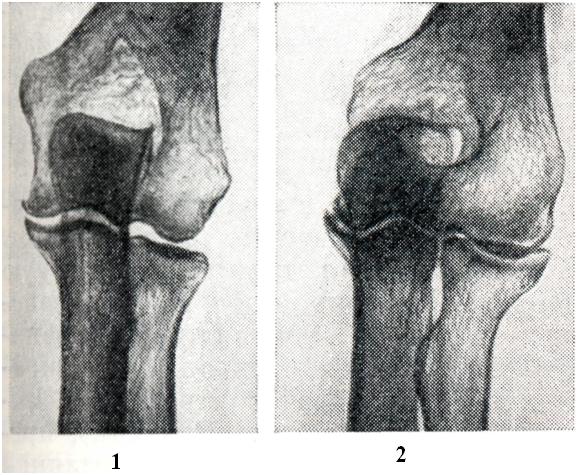

Рис. 11.

Запястно-пястный сустав I пальца: 1 — здорового человека; 2 — больного артрозом (рентгенограммы).

Рис. 12.

Локтевой сустав: 1 — здорового человека; 2 — больного артрозом. Выраженное сужение суставной щели (рентгенограммы).

Клиническая и рентгенологическая картина (рис. 11) — такая же, как и при артрозе двух предшествующих локализаций.

Артроз локтевого сустава наблюдается реже в связи с уменьшенной на него нагрузкой. Однако при некоторых видах труда, особенно с виброинструментами, создаются иногда условия для длительной микротравматизации этих суставов и для развития профессионального артроза (у шахтеров, кузнецов, литейщиков, каменщиков и др.), который проявляется резкими болями, усиливающимися после полного сгибания и разгибания в суставе. Вскоре наступает некоторое ограничение его подвижности. Часто отмечается грубый хруст в суставе при движениях. Кроме сужения суставной щели (рис. 12), подхрящевого остеосклероза и краевых остеофитов, часто наблюдаются суставные мыши, представляющие собой либо кусочки оторвавшегося и затем обызвествленного хряща (например, при расслаивающемся остеохондрите), либо проявление суставного хондроматоза.